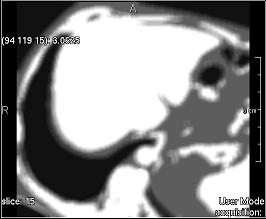

Deviation (simple)

../../../Modules/ML/MLFilter2/mhelp/Images/TextureFilterImages/deviation.jpg